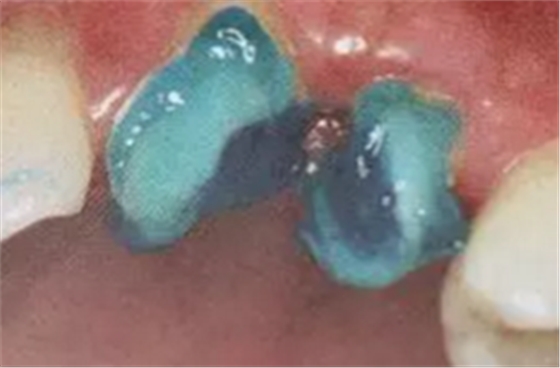

2. 清除根管壁殘留物

根管壁殘留物的存在直接影響纖維樁的粘接和固位,這也是導(dǎo)致纖維樁脫落的主要原因。

(根管內(nèi)殘留物)

個(gè)人見解:必要的情況下先開闊根管口建立一定的視角后,慢速手機(jī)上G鉆為引導(dǎo)鉆,由號(hào)遞增引導(dǎo)開闊通路;P鉆預(yù)備樁道,同樣需要由小向大號(hào)遞增,直到選擇好適合的號(hào)預(yù)備到規(guī)定測(cè)量的深度即可,再配合纖維樁系統(tǒng)中各型號(hào)纖維樁所匹配的樁道鉆,預(yù)備、修整成與纖維樁相適應(yīng)的樁道。

預(yù)備后根管壁上會(huì)不同程度的牙膠和封閉劑等殘留物,所以樁道預(yù)備前后建議X線片輔助檢查預(yù)備深度等情況,而殘留物也會(huì)很清晰地顯現(xiàn)。

根管銼去除殘留物,很難去除干凈,而備取樁道時(shí),禁止使用牙膠溶解劑(如:丁克除、氯仿)等有機(jī)溶劑去除殘留物,以防破壞根尖區(qū)牙膠的封閉和防止附著根管壁影響粘接。

(超聲去除根管殘留物)

通常此時(shí)以超聲潔牙機(jī)更換較細(xì)工作尖進(jìn)入根管(根管消毒沖洗液配合清潔工作后面會(huì)提到),徹底去除樁道根管壁上的附著殘留物,效果明顯。再配合X線片、根管顯微鏡輔助檢查清理的情況下更佳。